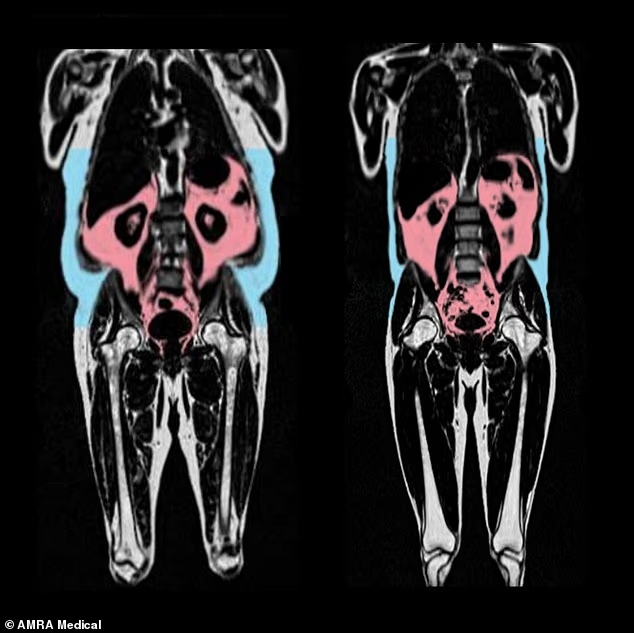

Για να καταλήξουν στα συμπεράσματά τους, οι επιστήμονες του Εργαστηρίου Ιατρικών Επιστημών του Ιατρικού Ερευνητικού Συμβουλίου (MRC) στο Λονδίνο ανέλυσαν μαγνητικές τομογραφίες από συμμετέχοντες της UK Biobank. Οι απεικονίσεις ολόκληρου του σώματος χαρτογράφησαν την ποσότητα και την κατανομή του λίπους, ενώ εξειδικευμένες απεικονίσεις καρδιάς και αγγείων αξιολογήθηκαν μέσω τεχνητής νοημοσύνης, προκειμένου να ανιχνευτούν ενδείξεις γήρανσης — όπως η σκλήρυνση ή η φλεγμονή των ιστών. Στη συνέχεια, σε κάθε συμμετέχοντα αποδόθηκε μια «βιολογική ηλικία καρδιάς», την οποία οι ερευνητές συνέκριναν με τη χρονολογική του ηλικία.

Ακόμη και τα αδύνατα άτομα ενδέχεται να διατρέχουν αυξημένο κίνδυνο εμφάνισης θανατηφόρου καρδιακού επεισοδίου, εξαιτίας του λεγόμενου «κρυφού» λίπους, που επιταχύνει τη γήρανση της καρδιάς, σύμφωνα με νέα, μεγάλη μελέτη. Το σπλαχνικό λίπος– όπως είναι γνωστό- βρίσκεται μέσα στην κοιλιακή κοιλότητα και συσσωρεύεται μεταξύ των οργάνων (στόμαχος, ήπαρ, πεπτικό, νεφροί κ.λπ.). Σε αντίθεση με το υποδόριο λίπος που μπορούμε να δούμε, αυτό το λίπος δεν είναι ορατό, με αποτέλεσμα πολλοί άνθρωποι που φαίνονται αδύνατοι να φέρουν εν αγνοία τους υψηλά επίπεδα.

Οι άνδρες με λίπος συγκεντρωμένο γύρω από την κοιλιά παρουσίαζαν μεγαλύτερες ενδείξεις πρόωρης γήρανσης της καρδιάς. Αντίθετα, οι γυναίκες με γενετική προδιάθεση να αποθηκεύουν λίπος στους γοφούς και τους μηρούς (το λεγόμενο γλουτομηριαίο λίπος, που δίνει το σχήμα «αχλάδι») φάνηκε να έχουν πιο υγιή και «νεότερη» καρδιά. Αυτό το λίπος που βρίσκεται στο κάτω μέρους του σώματος ενδέχεται μάλιστα να λειτουργεί προστατευτικά έναντι των καρδιοπαθειών, των εγκεφαλικών και του διαβήτη τύπου 2. Οι ερευνητές διαπίστωσαν επίσης ότι τα υψηλότερα επίπεδα οιστρογόνων σε γυναίκες πριν την εμμηνόπαυση συνδέονται με πιο αργή γήρανση της καρδιάς – κάτι που υποδηλώνει ότι η συγκεκριμένη ορμόνη μπορεί να παίζει προστατευτικό ρόλο.